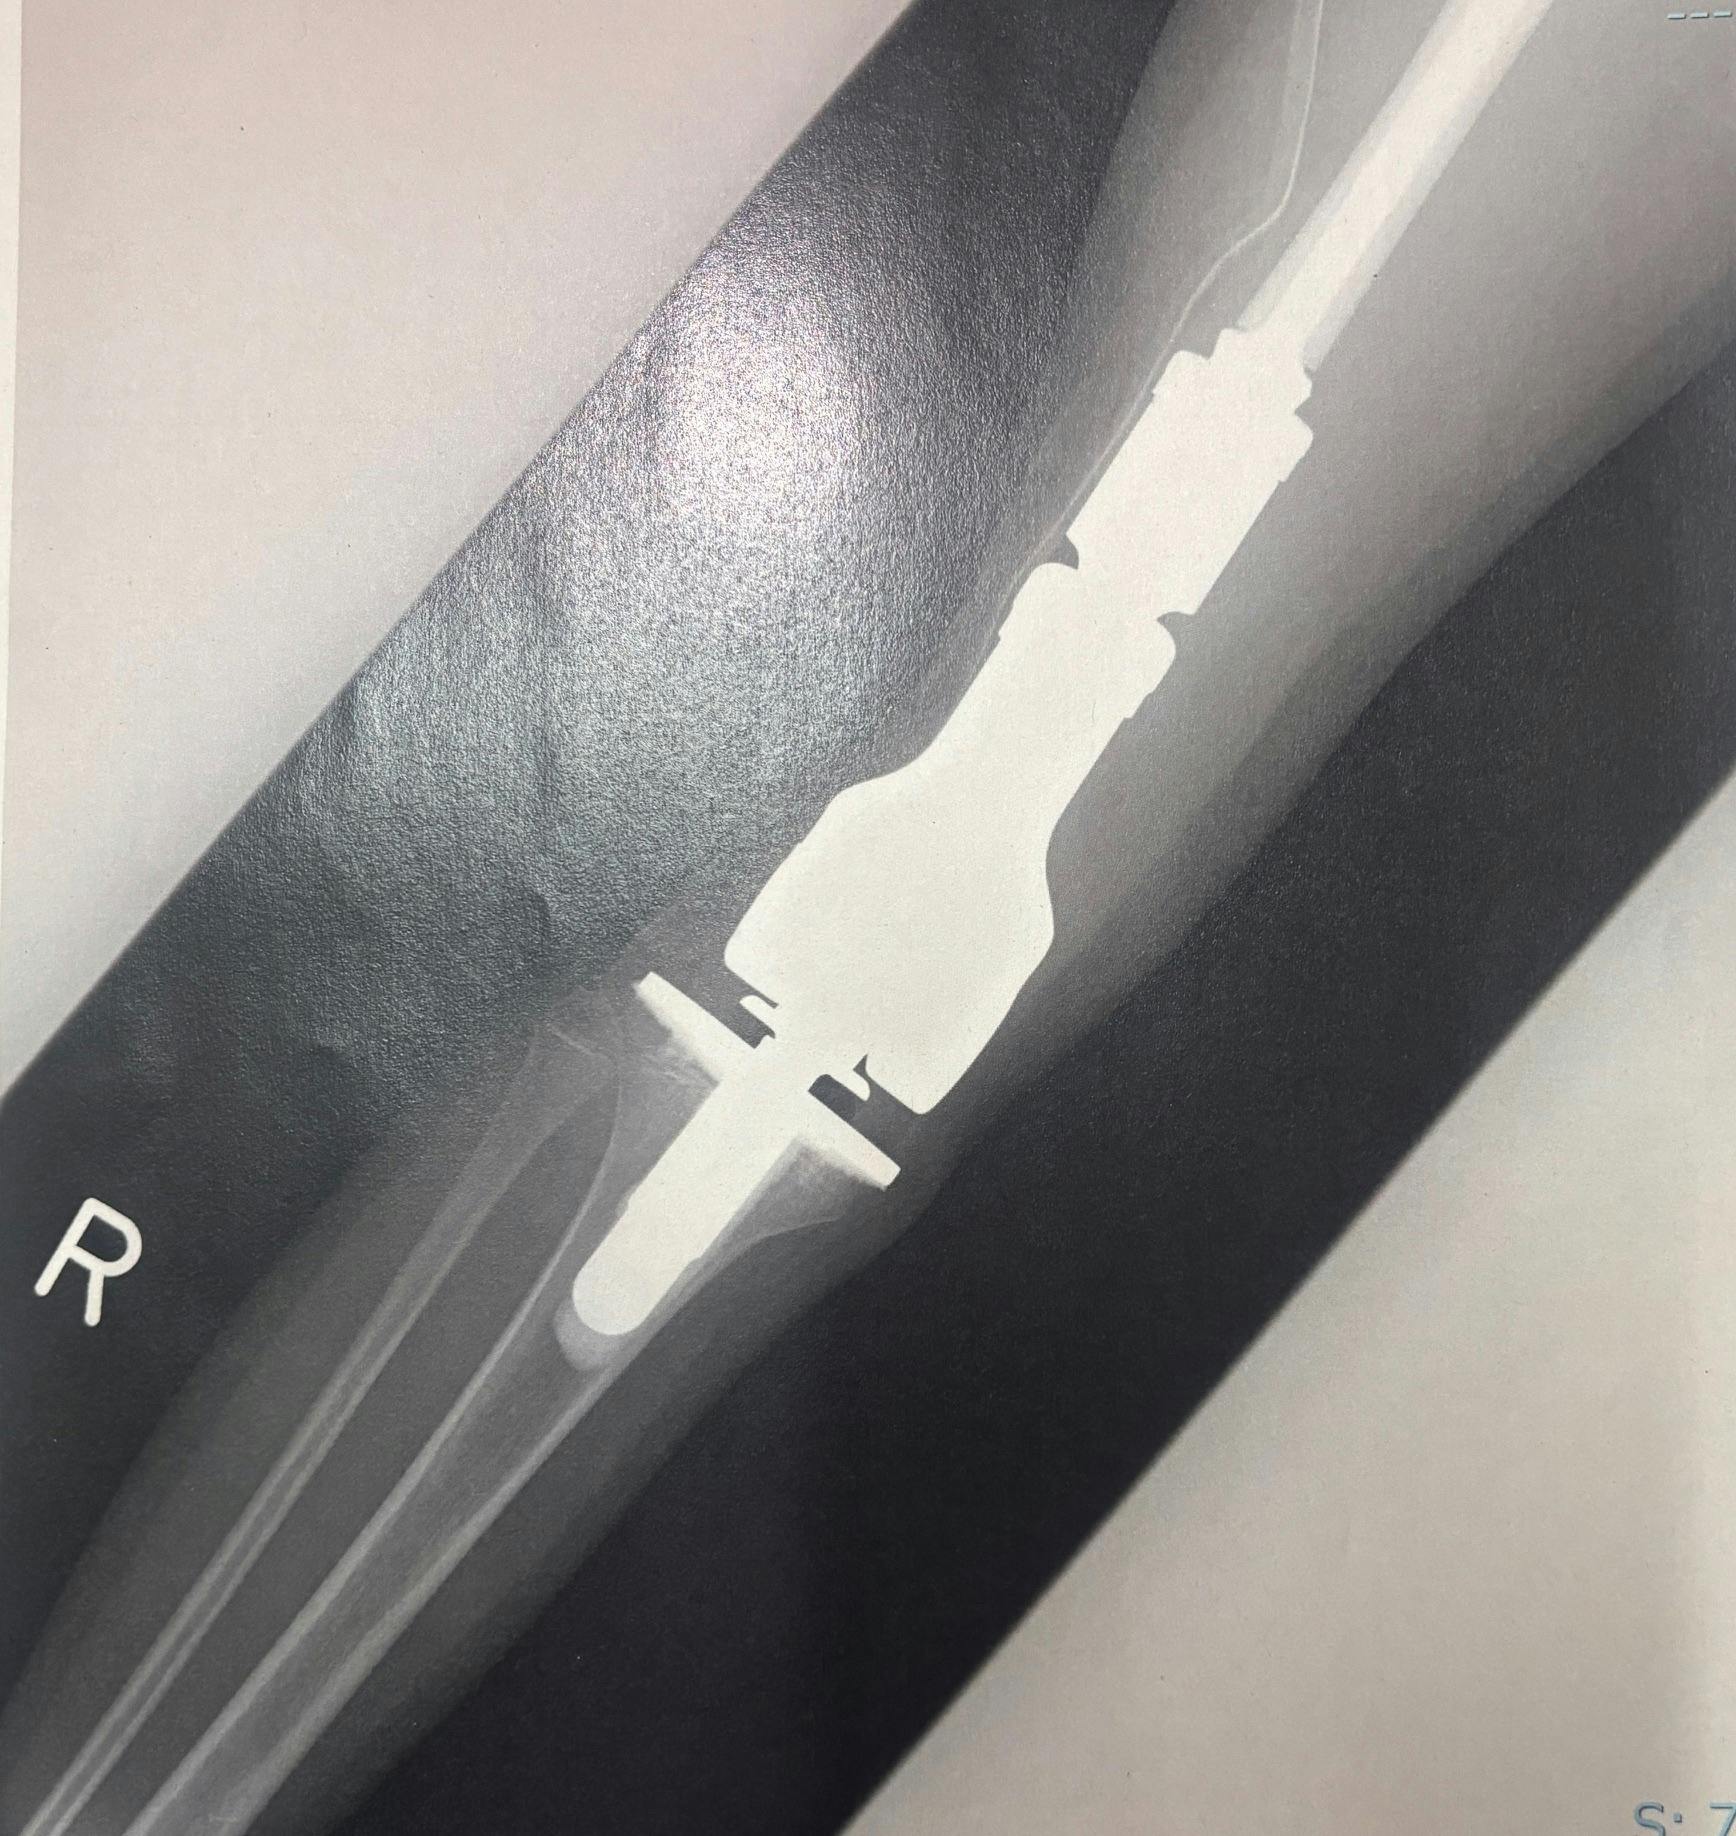

実際のレントゲン写真

実際の手術後の人工関節のレントゲン

腫瘍用人工関節と一般的な人工関節の違い!

2025/08/18 16:13腫瘍用人工関節と一般的な人工関節の違い 2025年8月18日娘の骨肉腫が発覚し、これまでの治療として、数種類の抗がん剤治療と膝の人工関節置換術をやってきましたまた、右足が人工関節になる事により、先生からは全力で走る事や激しいコンタクトスポーツ(柔道やラグビー・サッカーなど)をできないと宣告されましたなんとかソフトボールや空手を病気前の状態に近づくぐらい全力でできないかと思い、今回のクラウドファンディングプロジェクトを立ち上げました!その後、知人などに人工関節になる事でスポーツができない・できにくい事になると話をしていると『大丈夫!私の知り合いの人、人工関節の人いてるけど今はばりばりテニスしてる人いるよ』『だから娘さんも大丈夫!』『you tubeで人工関節の男の子、力強い素振りしてたよ、中学生の男の子は膝の人工関節で3000m走ってたよ』など励ましの言葉をたくさんいただきます。ありがとうございますしかし、次女の腫瘍での人工関節とスポーツ等で膝を痛めての人工関節は大きく違いますQ:腫瘍用の人工関節と通常の人工関節との違いは何ですか?A:関節の表面だけを削って人工物に置き換える通常の人工関節に比べて、腫瘍用人工関節は、広範囲に切除した悪い腫瘍部分を補わなければならないことが一般的であるために、より大きなものになります。多くの骨と筋肉を切除するのが腫瘍用人工関節の為、より日常に戻る事、走る事、運動する事が難しいとされておりますもちろん、どちらの人工関節も術後は長期間のリハビリが必要となり、日々の生活に多少の支障はでてきます。今回は『人工関節でも違いのある人工関節がありますよ』という記事になります。決して、軽い、重いとかを訴えているのではありません。どちらも術後は大変です。ただ、認識としてそういう2つのパターンがある事を知っていただけたらなという思いです。人工関節の違い実際の人工関節のレントゲンまた、人工関節は体の内部の器具ですから、外見(例えば服を着たりしている)からは全くわかりません。ですので、火事が起こったり、地震などの災害が起こったりした場合、走ったり、しゃがんだり、迅速に動く事ができない事もあります全力で走る事だけでなく、この点も課題として取り組んでいきたいと思っております。早くて、今月中に退院できそうです決して良い退院ではないのですが、やるべき事はすべてやっていただいたと思っております。病院・先生・看護師さんには本人・親と感謝しております。退院してすぐの学校という訳でなく、自宅療養をしながら状況をみて学校にも復学する予定です。ご支援・ご声援、本当にありがとうございます追伸:9月4日に補助器具に製作会社、ダイヤ工業株式会社様とサンプル器具の装着・面談を予定しております!また、10月には次女を連れて、岡山にあるダイヤ工業本社に連れて行き、あらゆるデータを測定ししてもらいます。こちらも随時、活動報告させていただきます! もっと見る